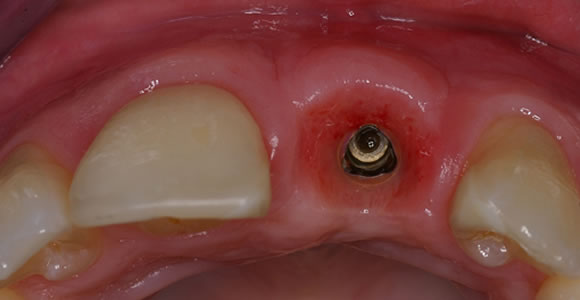

Einzelzahnversorgung

Fehlende Zähne können in jedem Alter auftreten. Auch Jugendliche können schon Zähne verlieren. Ursache dafür sind häufig Karies oder Unfälle im Straßenverkehr und beim Sport. Bei vielen Menschen sind einzelne Zähne im Unter- oder Oberkiefer von Natur aus gar nicht angelegt. Oft sind davon die kleinen Schneidezähne im Oberkiefer sowie die kleinen Backenzähne im Unter- und Oberkiefer betroffen. Der fehlende Zahn einer einzelnen Zahnlücke kann durch ein Implantat ersetzt werden. Da die benachbarten Zähne nicht abgeschliffen werden müssen, wie es beim alternativen Zahnersatz notwendig wäre, bleiben sie ohne Trauma.